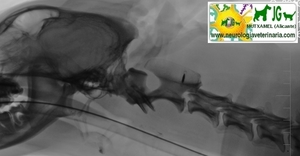

Radiografía digital (no digitalizada) de un cocker inglés mostrando el diente del axis. |